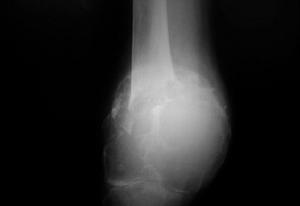

骨巨细胞瘤的好发部位为股骨下端和胫骨上端(膝关节周围),其次为肱骨近端和桡骨远端,其他部位有椎体、骶骨、髂骨、腓骨近端、胫骨远端等等。

【资料】骨巨细胞瘤(giant cell tumor ,简称GCT)为骨原发的良性侵袭性肿瘤,占原发骨肿瘤的20%,早期将其分在低度恶性中,后分为中间性(良恶性之间),现在的分类为良性侵袭性肿瘤(3期)。可以看出骨巨细胞瘤生物学行为复杂,多变。骨巨细胞瘤病因不明。